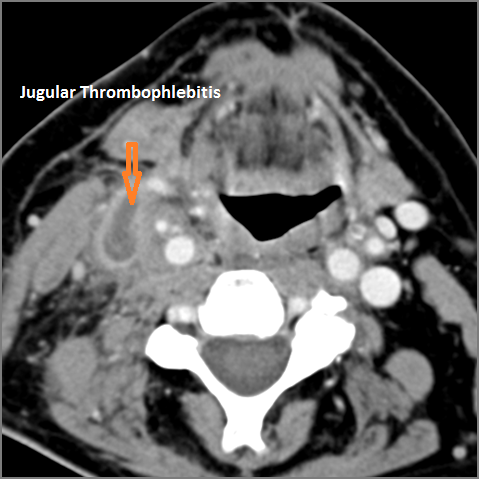

Vascular Findings

There is evidence of thrombus, thrombophlebitis or other occlusive or inflammatory process of the jugular vein or smaller venous tributaries. [Yes/No]

Venous thrombosis or thrombophlebitis